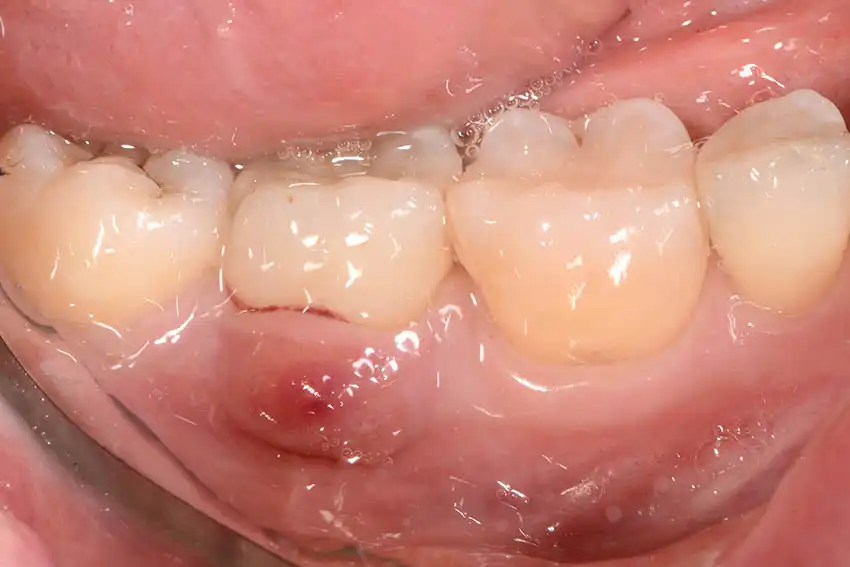

Un ascesso parodontale è una raccolta di pus che si forma nei tessuti che sostengono il dente, come gengiva, legamento parodontale e osso alveolare. A differenza dell’ascesso dentale (che ha origine dalla polpa del dente), l’ascesso parodontale nasce dalle strutture che circondano il dente, spesso in presenza di malattie gengivali trascurate. Immagina una piccola sacca infetta che si crea tra dente e gengiva: è lì che si accumulano batteri, cellule morte e pus, causando dolore, gonfiore e talvolta febbre.

- Presenza di una “bolla” o rigonfiamento biancastro sulla gengiva

In alcuni casi, può comparire anche febbre o malessere generale, segnale che l’infezione si sta diffondendo.